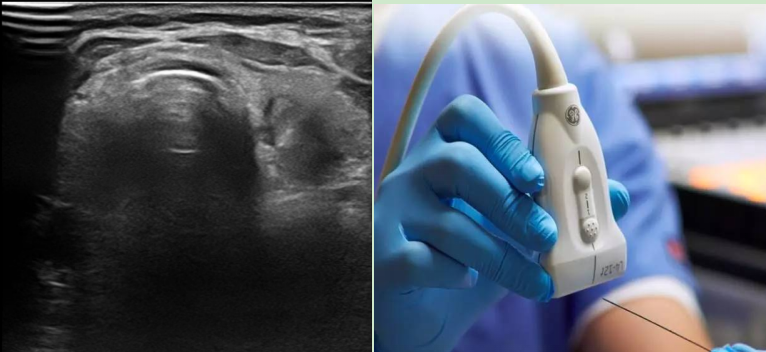

国考晋位升级之一科一报道| 超声引导下穿刺活检——精准诊断的“微创利器”

超声引导下穿刺活检是一种在超声影像技术实时监控下,通过细针穿刺进入人体组织或器官,获取少量细胞或组织样本,然后进行病理检查以明确疾病诊断的方法。简单来说,就像是在超声这位“导航员”的指引下,让一根小小的针准确地抵达病变部位,取出“情报”,帮助医生判断疾病的“真面目”。

超声引导下穿刺活检针是什么样?

目前超声引导下穿刺活检包括组织学和细胞学活检,细胞学活检主要应用在甲状腺结节的病理诊断,穿刺针直径为0.6mm,针细,操作安全,并发症少等优点;组织学活检适用于乳腺、淋巴结、肾脏、肝脏、前列腺等脏器肿物,穿刺针为内槽式切割针,直径分别为1.2mm,1.6mm,诊断准确性更高。